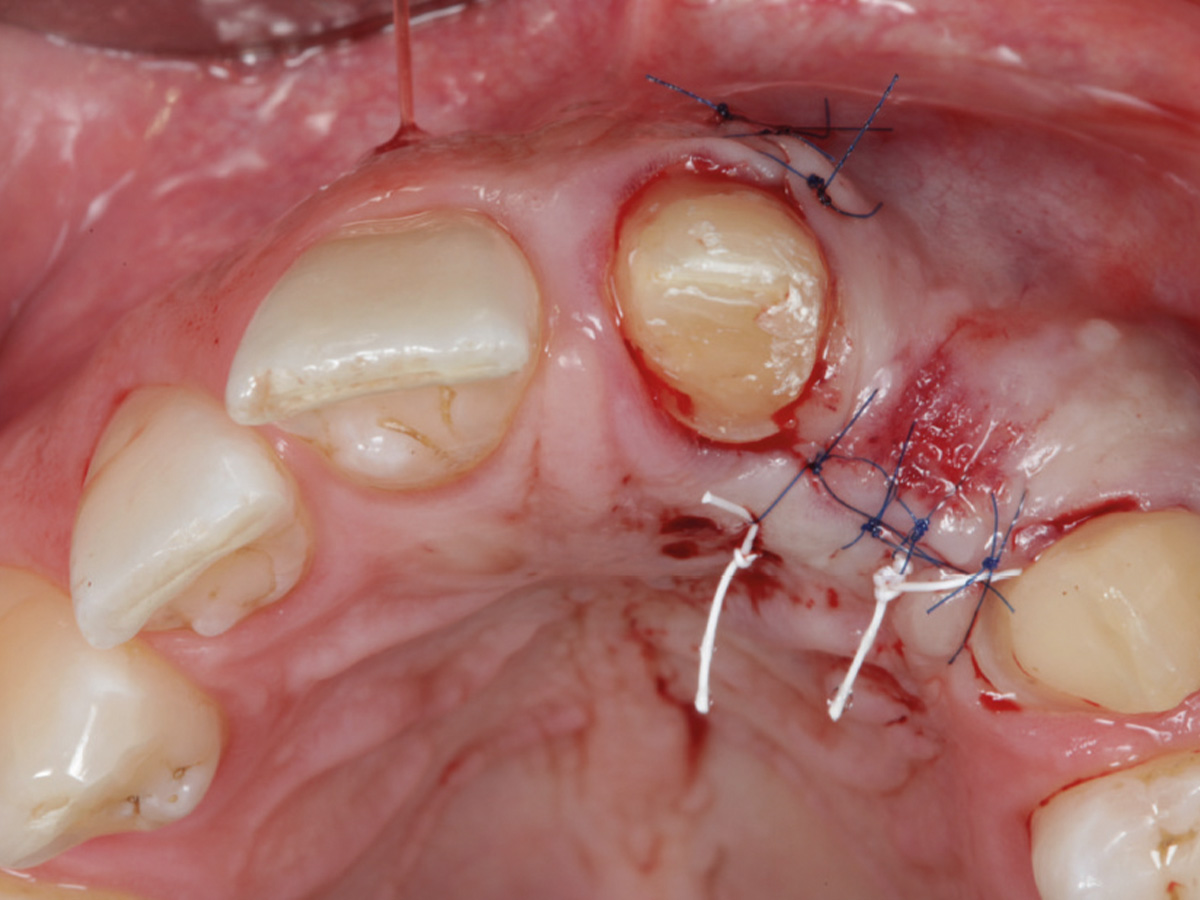

Abbildung 7

Der Weichgewebsverschluss muss spannungsfrei erfolgen. Einsatz von mikrochirurgischen Techniken.

Abbildung 8

6 Monate nach der Augmentation.